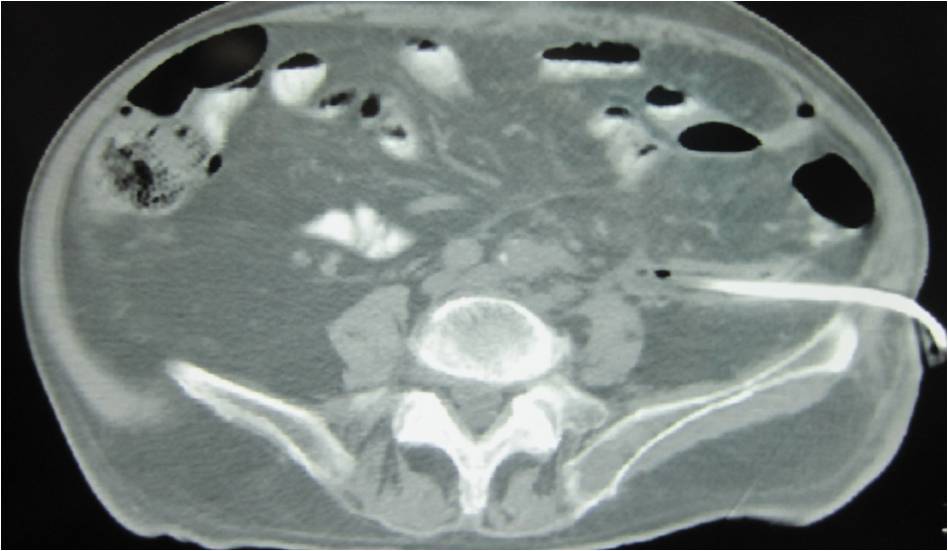

- Placement of a nephrostomy and sump caheter through the greater sciatic foramen into a deep pelvic abscess.

- Paracentisis of a deep pelvic abscess

- Successful catheter placement in a deep pelvic abscess